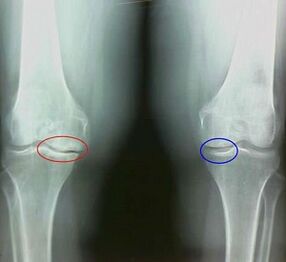

Osteoarthritis is a dystrophic degenerative process associated with the destruction of the cartilage tissue of the joint.The cartilage is gradually destroyed, dry, the distance between the bones of the joint decreases, which is the cause of the pain.In serious forms, destruction affects bones.They become more porous, lose their density, become fragile.

For example, what is the difference between arthritis and osteoarthritis of the knee joint?With arthritis, the synovial shell of joint tissues occurs.This causes an increase in the temperature of the joint.

The joint swells, a persistent pain syndrome develops, intensifying during movement.With osteoarthritis, pain only occurs after physical activity, you can hear a characteristic crunch or clicks in the joint, gradually the joint is distorted and loses mobility.

Osteoarthritis is developing gradually and is not noticeable in the first stages.Often, he is taken for physical fatigue.The chronic form of osteoarthritis is also called osteoarthrosis.To the question of what is worse - osteoarthritis or osteoarthrosis, the answer is obvious.The last option is a consequence of the development of osteoarthritis and its acute shape.

- The pain appears after physical activity, with sudden movements, turns, inclinations, after rest, pain passes;

- A characteristic crunch in the joints is noted;

- Pain after prolonged rest, which goes within 15 to 20 minutes depending on mobility (this is associated with stagnant phenomena occurring in the joint);

- worried about hardening pain at night due to venous stagnation;

- The inflammatory form of pathology is accompanied by edema and pain;

- The joint is distorted, its mobility decreases.